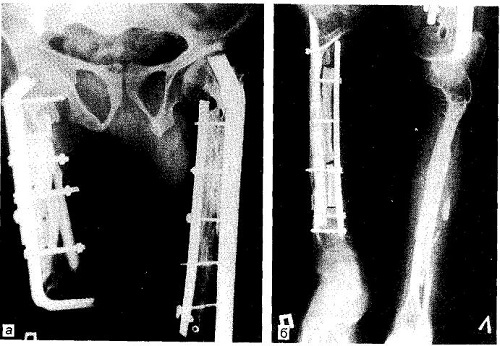

Лечение фиброзной дисплазии кости предполагает лишь оперативное вмешательство, при котором осуществляется резекция очага поражения независимо от его размеров в пределах здоровых тканей, с дальнейшим замещением дефекта гомотрансплантатом.

Ослабление клинических симптомов данного заболевания возможно в результате проведения определенных ортопедических процедур: остеотомии, пересадки костей и кюретажей.

Назначают проведение данных вмешательств в случае прогрессирующих деформаций, многократных и долго не срастающихся переломов, а также при болевом синдроме, избавиться от которого с помощью обычных лекарственных средств не удается.